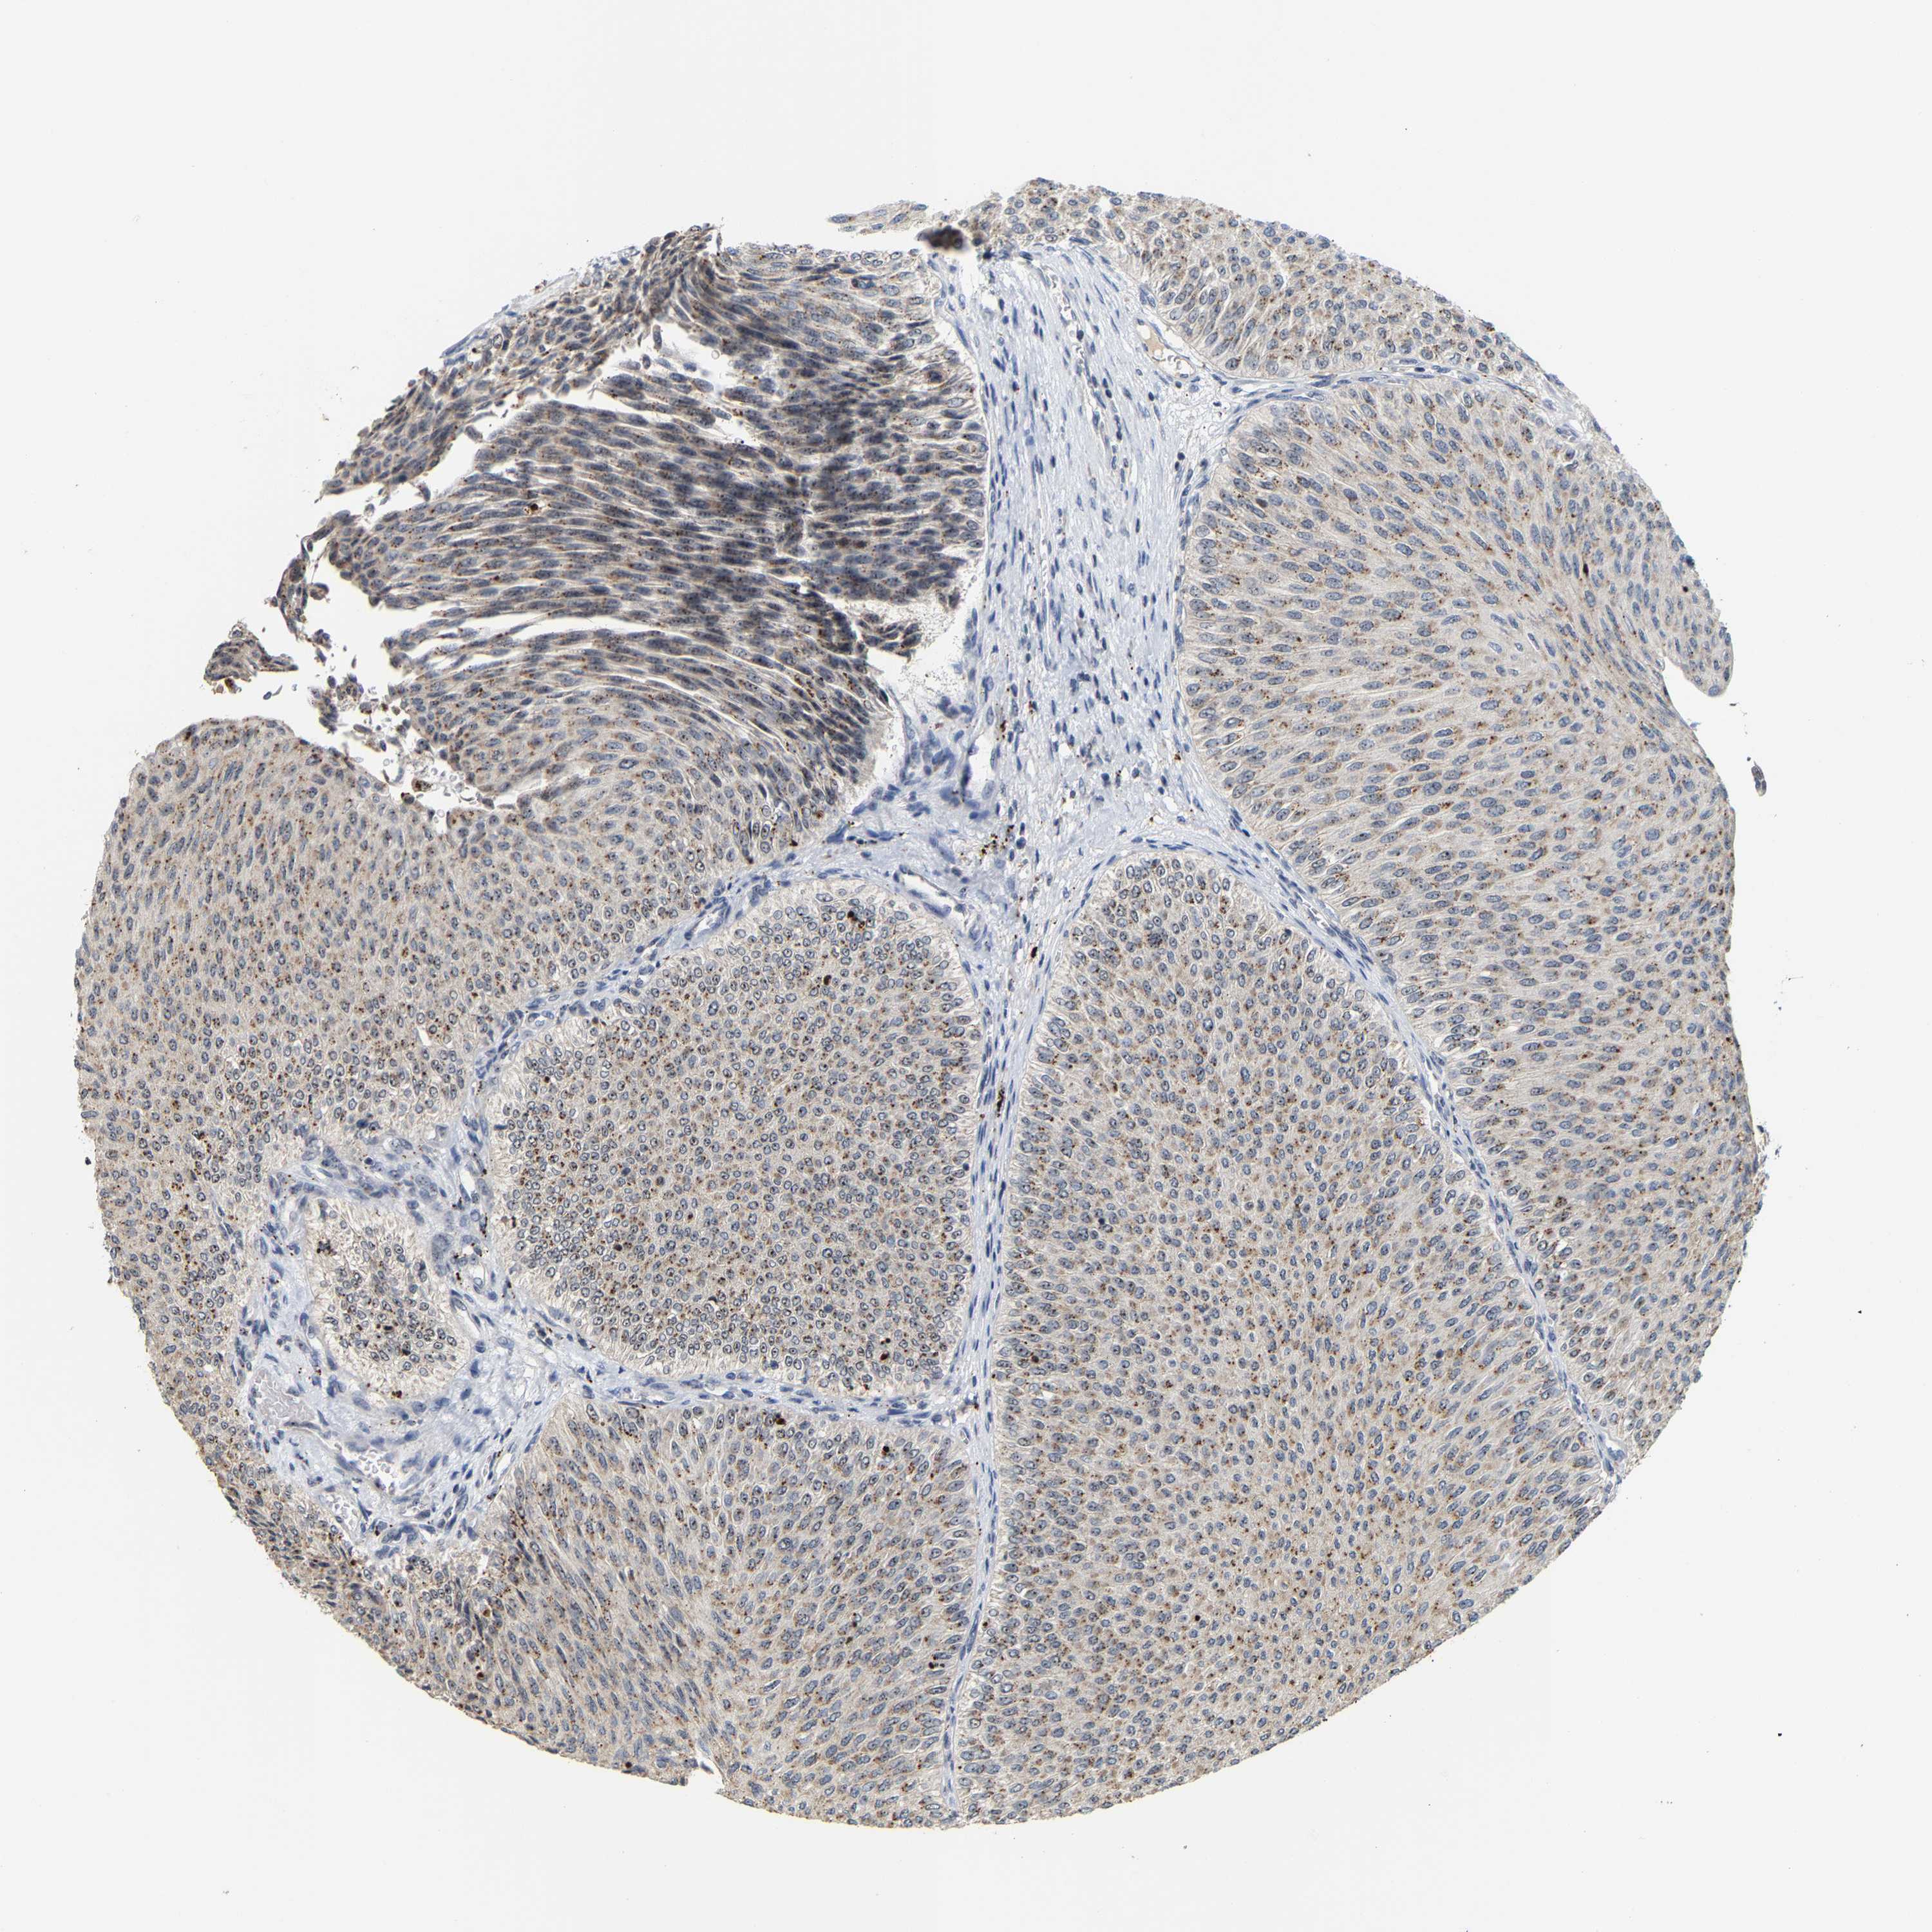

UROTHELIAL CANCER - Protein expressioni

A mouse-over function shows sample information and annotation data. Click on an image to view it in a full screen mode. Samples can be filtered based on level of antibody staining by selecting one or several of the following categories: high, medium, low and not detected. The assay and annotation is described here.

Note that samples used for immunohistochemistry by the Human Protein Atlas do not correspond to samples in the TCGA dataset.

Antibody stainingi

Antibody staining in the annotated cell types in the current human tissue is reported as not detected, low, medium, or high, based on conventional immunohistochemistry profiling in selected tissues. This score is based on the combination of the staining intensity and fraction of stained cells.

Each image is clickable and will lead to virtual microscopy that enables deeper exploration of all samples and also displays staining intensity scores, fraction scores and subcellular localization as well as patient and tissue information for each sample.

Antibody HPA018472

Antibody HPA021062

Urothelial carcinoma, Low grade

Urothelial carcinoma, High grade